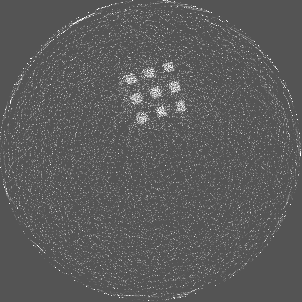

Figure 5 illustrates a single slice spectral reconstruction of the Ti scaffold. Varying levels of streak artefacts can be seen across the spectral reconstructions. The spectral reconstructions for the energy ranges 35 to 80 keV, 55 to 80 keV, and 62 to 80 keV shown in figure 5, exhibit reduced streak artefacts. A region-of-interest (ROI) analysis was performed in the immediate vicinity of the metal region where the streaks are more pronounced. Average attenuation coefficent of air close to zero conveys less regional noise/artefacts. The regional average attenuation coefficient (μROIsubscript𝜇𝑅𝑂𝐼\mu_{ROI}) of the non-metal (air) region in 55 to 80 keV reconstruction (figure 5c) shows reduced artefacts. Even though minor streaks and statistical noise appear in figure 5d due to photon limitation, the artefacts are less pronounced in comparison to the wide energy acquisition in figure 5a.

Refer to caption

(a) 15 to 80 keV

(b) 35 to 80 keV

(c) 55 to 80 keV

(d) 62 to 80 keV

Figure 5: Single slice spectral reconstruction of Ti scaffold sample. μROIsubscript𝜇𝑅𝑂𝐼\mu_{ROI} is 0.246, 0.030, 0.008 and 0.103 for the circular ROI in (a), (b), (c) and (d) respectively.